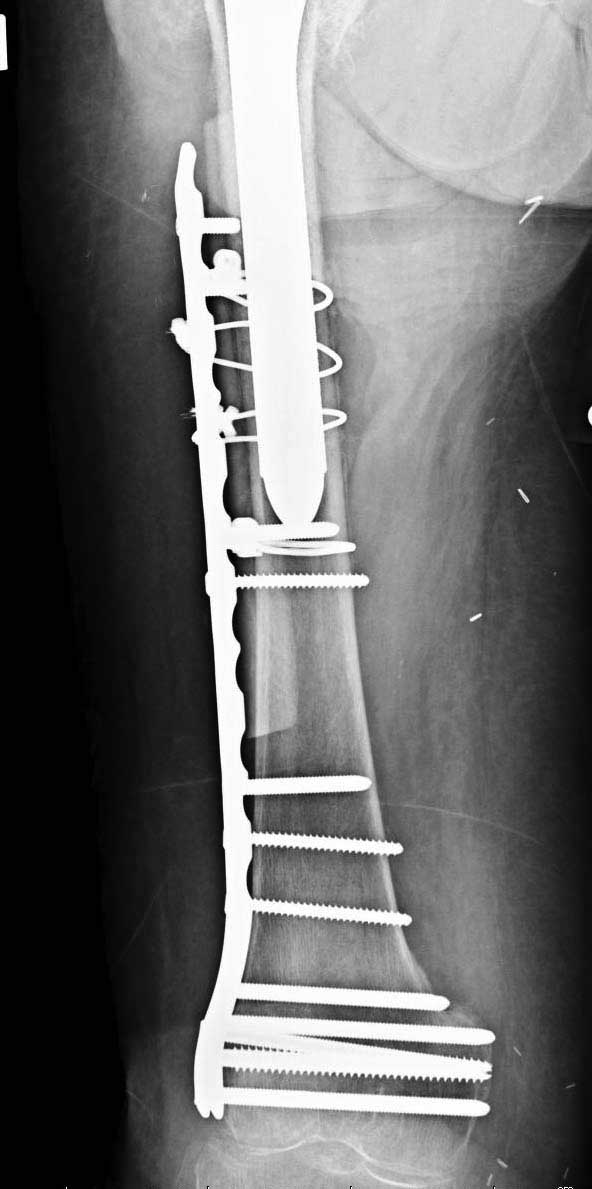

Сеньоры-пэры ревизировали гвоздем, шуруп поставили по той же дорожке, только поглубже. Да еще и bone graft не пожалели. "Результат" уже был через 2 дня.

Если сохранять головку - думаю надо было в валгусе фиксировать перелом гвоздем, или DCS, т.к. все-равно разрезали, чтоб достать DHS.

No comment.

End of story.

Неужели фиксация протеза бесцементная? Да и чашка не запрессована как надо.Грустно(

Эт -ж биполяр:)) Ножка цементная. Страйкеровский Exeter.1

биполярный эндопротез все же не лучший выбор для данной ситуации.судя по снимкам мышечные прикрепления на вертелах утрачены.Возможно здесь подошла бы более стабильная конструкция.Ваше мнение?

а куда делся фрагмент большого вертела? Очевидно,

Если среднеягодичная мышца не рефиксирована, то ничто не держит протез во впадине и это закономерный результат.

Третья операция-продолжения усилии “синьорами пэрами” по разрушению нормальной анатомии. Крест на головку! По видимому возраст позволяет биполярную конструкции, и при дефекте calcar пошли на обычный цементный. Ягодичные мышцы потеряли связь с вертелом, т.е. отсутствует верхний удержатель, и результат “a Big Screw Up!” Снимки вызывают головокружение!

Если хирурги не устали от своих “творчеств”, тогда можно ре-оперировать с calcar replacement stem, и собрать остаток ягодичных мышц. Глубина и отстутствие артроза позволяет применить любой, биполярный или тотальный, хотя принять решение можно после ревизии ацетабулума.